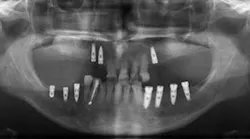

The purpose of this study was to evaluate changes in sinus dimensions immediately postoperatively and one year later using a composite of bovine-derived xenograft and autogenous bone for lateral bone augmentation of the maxillary sinus. Patients who underwent lateral wall sinus augmentation procedures without concomitant implant placement were considered for this retrospective analysis if they had three consecutive panoramic radiographs: pretreatment (T0), immediately after lateral wall sinus augmentation (T1), and approximately one year postoperatively (T2). Eighteen subjects ages 47 to 69 years were included.

The surgical protocol included grafting with a composite of bovine-derived xenograft and autogenous bone (9:1 ratio). Digital panoramic radiographs were transferred into measurement software, and the following measurements were performed: (1) vertical distance from the alveolar crest to the height of the augmented material, (2) sagittal area of the grafted area, and (3) vertical distance from the alveolar crest to the roof of the maxillary sinus.

The results showed that the mean overall sinus sagittal area was 1,330 ± 481 mm2 prior to the grafting procedure, when it decreased to 858.2 ± 436 mm2 (range, 380.7 to 2,134 mm2) immediately postoperatively (P = .0035) and remained stable at one year (mean, 882.2 ± 384 mm2, P > .05). Similarly, the overall area of the grafted material at the time of surgery was 468.3 ± 208 mm2 and was only slightly reduced at one year (422.2 ± 193 mm2). The midsagittal graft height at T1 (mean, 20.67 ± 4.5 mm) was insignificantly and minimally reduced at one year (mean, 19.35 ± 4.9 mm).

The authors concluded that the linear dimensions of composite bone-derived xenograft/autogenous bone grafts following lateral wall sinus augmentation exhibited minimal changes during the eight- to 12-month healing period.